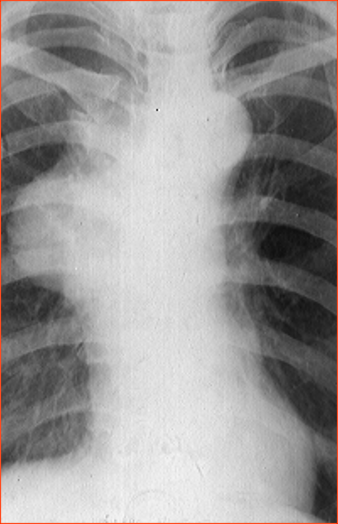

Rx toracică, incidență P-A

DESCRIERE:

la niv. întregului hemitorace stg → opacitate extinsă, nesistematizată, de intensitate mare, omogenă

caracter retractil → tracționează traheea și mediastinul de partea afectată

fără bronhogramă aerică

duce la micșorarea spațiilor intercostale

la niv. hemitoracelui controlateral → hipertransparență compensatorie

DX: atelectazie prin NBP central endobronșic (pe bronhia principală stg)

DD: pleurezie masivă → caracter expansiv